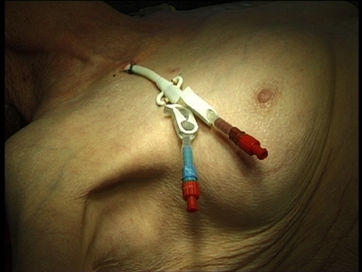

Portkammern sollen im Trigonum deltoideo-pectorale (Mohrenheim´sche Grube) liegen, bei Frauen ist darauf zu achten, dass sie nicht unter dem BH-Träger liegen und keinesfalls auf dem Brustansatz.

Die weiblich Brust hat die Eigenschaft, im Stehen der Schwerkraft zu folgen, und zwar umso mehr, je schwerer die Brust und je älter die Patientin. Der Port wandert dann mit der Brust nach unten und disloziert den Katheter aus der Vene. An den erweiterten Venen am linken Oberarm und Thorax erkennt man auch eine weitere Komplikation: die Thrombose der Vena subclavia.

Im Röntgen sieht man den dislozierten Katheter und die Kontrastmittelextravasation ins Mediastinum. Dorthin wurde auch das hochgradig gewebetoxische Adriamycin infundiert.